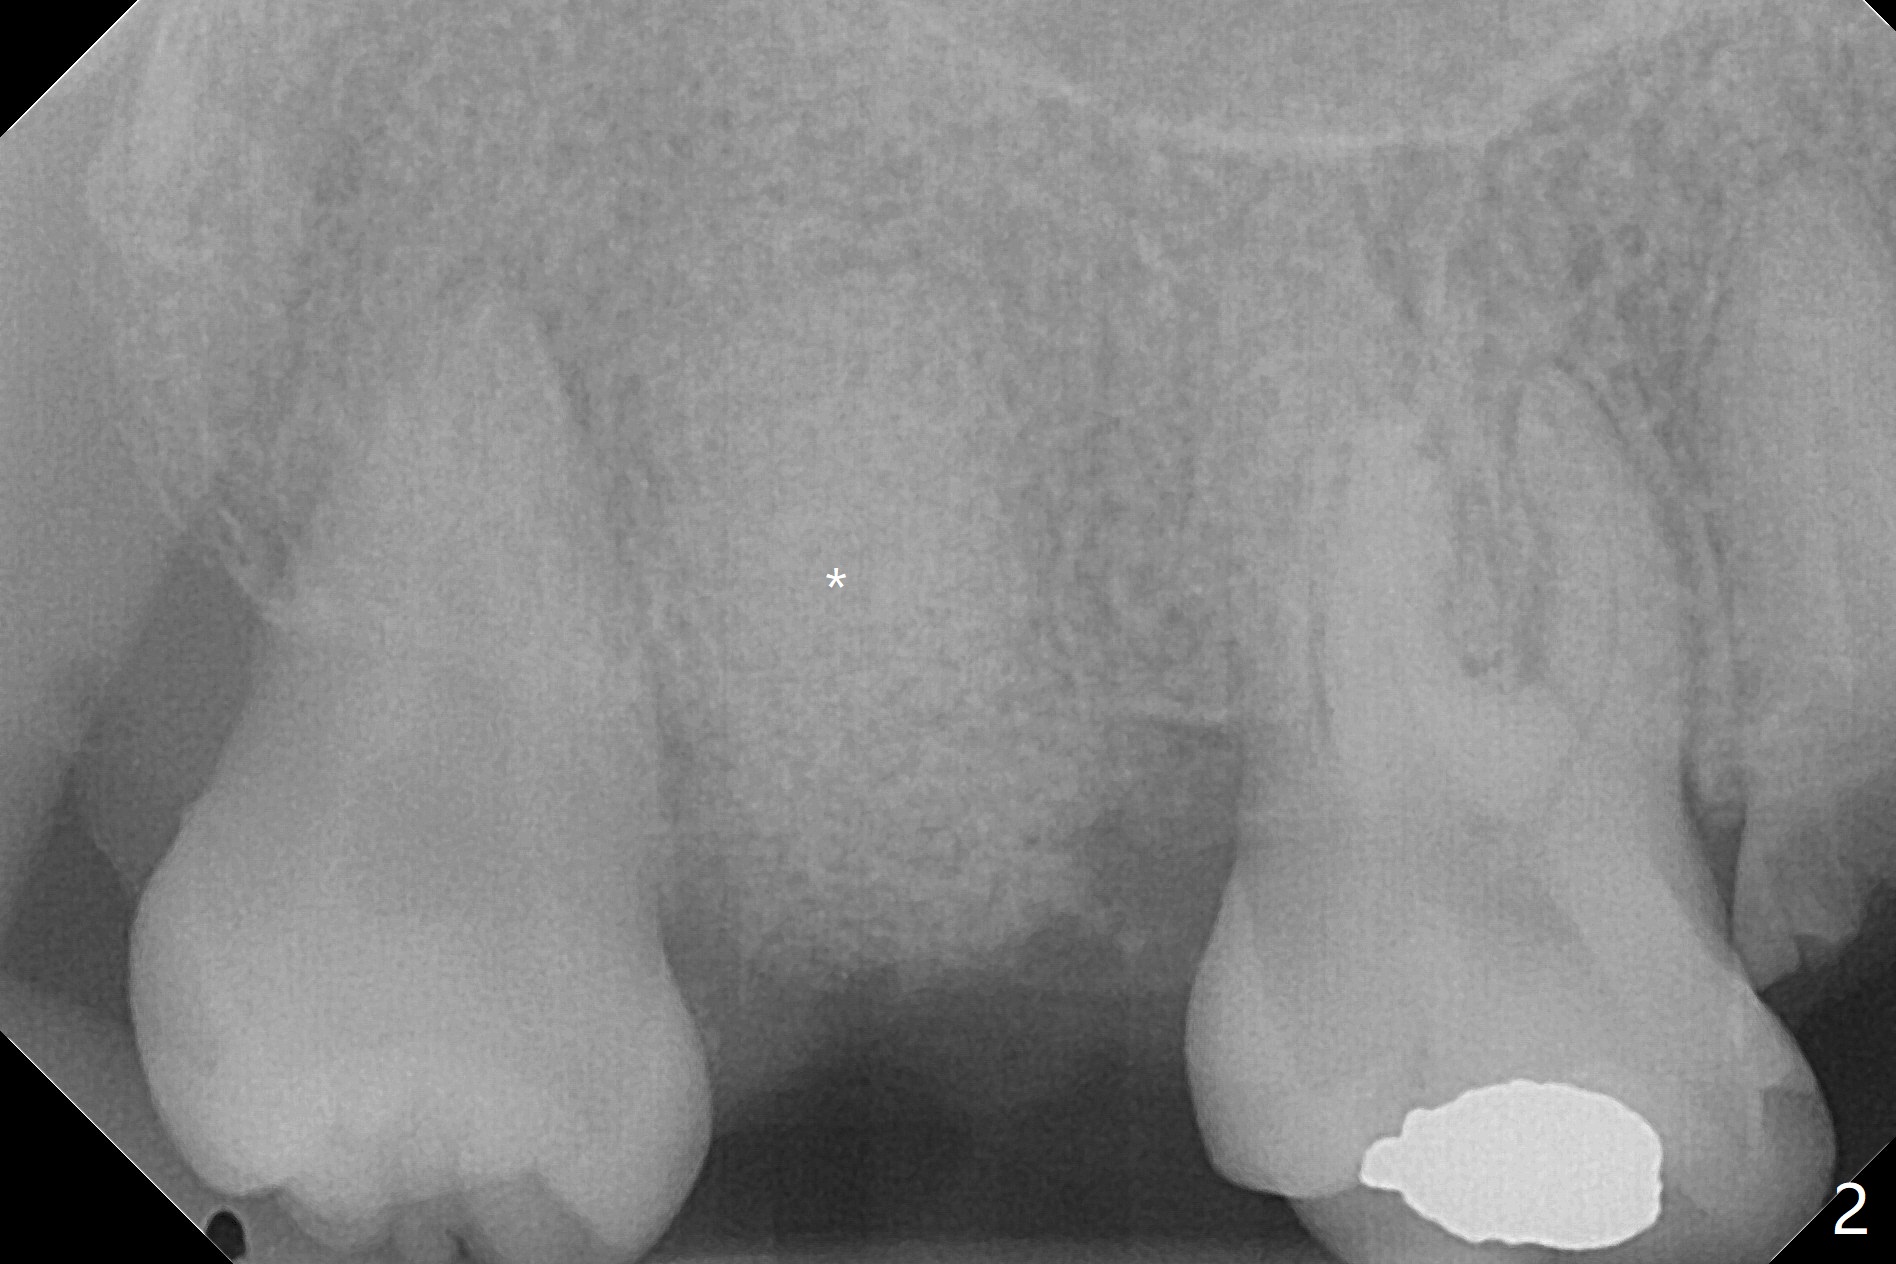

38岁女,牙列不全,咬合塌陷,因右上7疼痛就诊(图一),十分恐惧治疗,虽然残根好像不大,骨粉填入不少(图二:*;使用.5毫升GEM21S,异体骨和合成材料(ß-TCP (beta tricalcium phosphate)),使用不带齿刮匙或者充填器压入牙槽窝。使用GEM Cap(9-12月吸收膜)关闭牙槽窝开口(图三:C),牙周胶水固定膜。由于右下7延申(图一(箭头),四),没有空间放置牙周或者树脂敷料。膜术后4天脱落(加用缝线可以避免早期脱落),7天伤口明显缩小(膜早期脱落好处,图五,与图三对比),白色的骨粉仿佛稳定,所以没有做特殊处理,观察。No Caries GEM21S Xin Wei, DDS, PhD, MS 1st edition 01/26/2021, last revision 02/01/2021